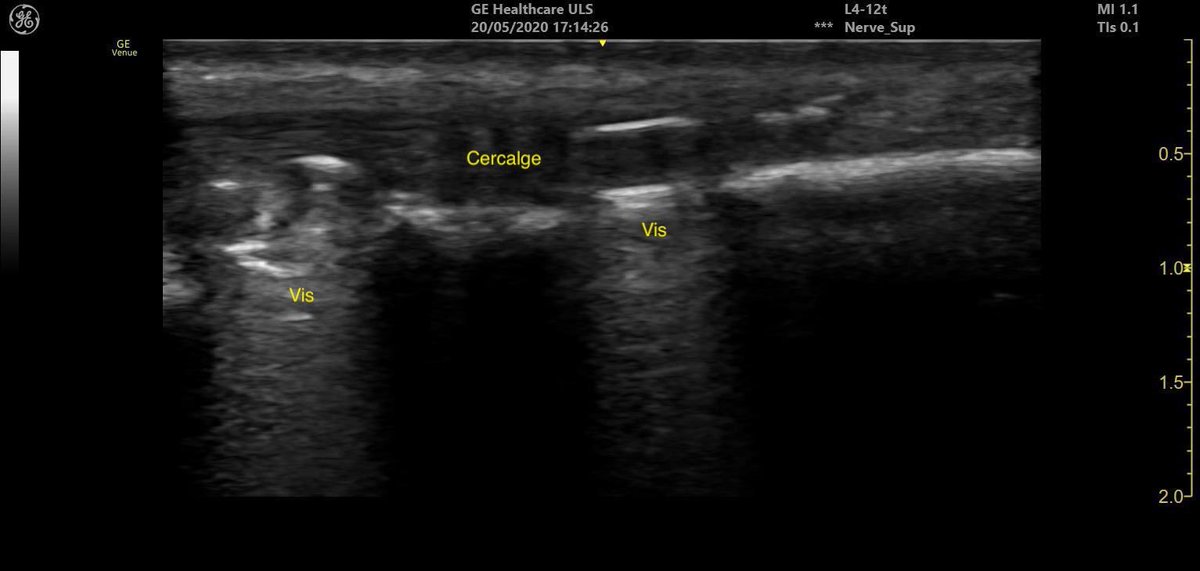

➡️tronculaires

➡️cathéters périnerveux à domicile

✅Test du nouvel échographe sans fil Vscan air👍👍 @generalelectric